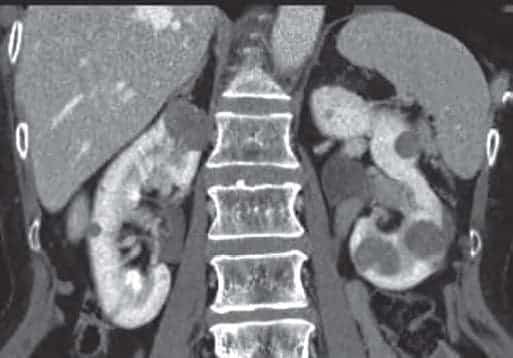

3) Мультиспиральная компьютерная томография с контрастированием (МСКТ)

является золотым стандартом. Этот метод позволяет точно определить границы опухоли, ее диаметр, положение, а также прорастание опухоли в соседние ткани. Точность в диагностике составляет 95 процентов. Мультиспиральную КТ органов грудной клетки выполняют при подозрении на метастатическое поражение при обычной рентгенографии.

Рисунок 2. КТ картина папилярно-клеточной карциномы почек